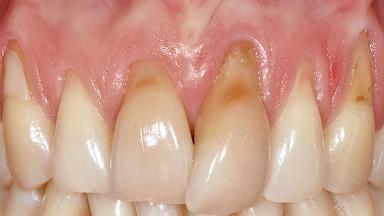

Implant Placement in the Esthetic Zone and Coverage of Multiple Gingival Recessions

This case illustrates use of a modified ‘tunnel’ technique, which has been shown to be highly effective in root coverage procedures. The tunnel technique is used to achieve soft-tissue augmentation across the anterior area, including the planned implant site, using collagen matrix as grafting material. The patient is a 47-year-old woman with high esthetic expectations. Her main concern was the appearance of the anterior teeth and their “elongation”.

Soft Tissue Anatomy Intact Defective